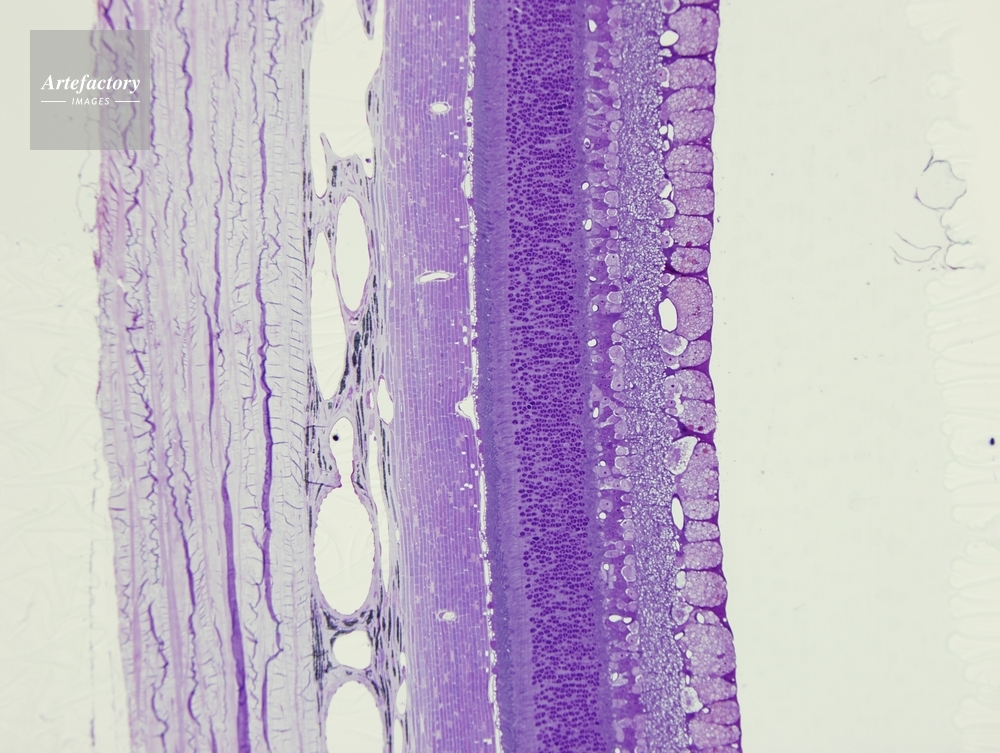

| 作品タイトル | ネコ,網膜 | モデルリリース | なし | |

| 作家 | OLYMPUS CORPORATION Technolab | プロパティリリース | なし | |

| ソース | ピクセル数 | 3455px × 2602px | ||

| 撮影地 | 印刷サイズ | 20.3cm × 15.3cm | ||

| 撮影年月日 | 2007/5/30 | データサイズ | 4.7MByte | |